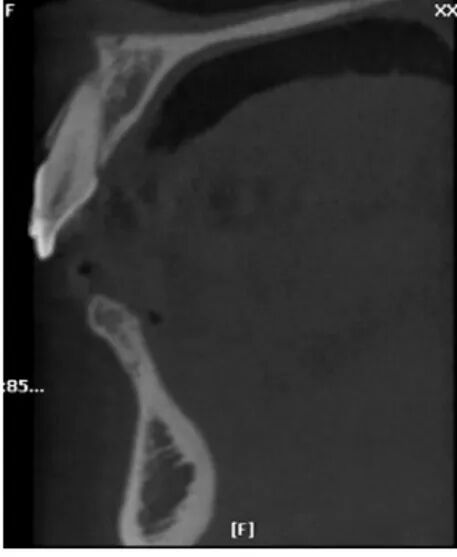

图21 术前CBCT片矢状位

显示在上颌前牙区的牙槽骨高度明显不足

图22 术后CBCT片矢状位

显示植骨后种植体植入,唇侧有明显植入骨影像